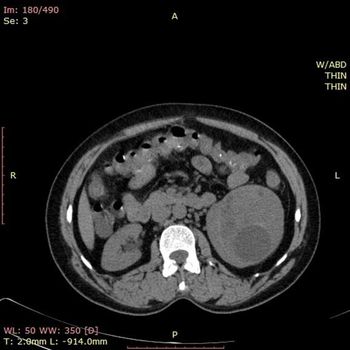

Case History: A 33-year-old patient presented with history abdominal discomfort for 5 months.